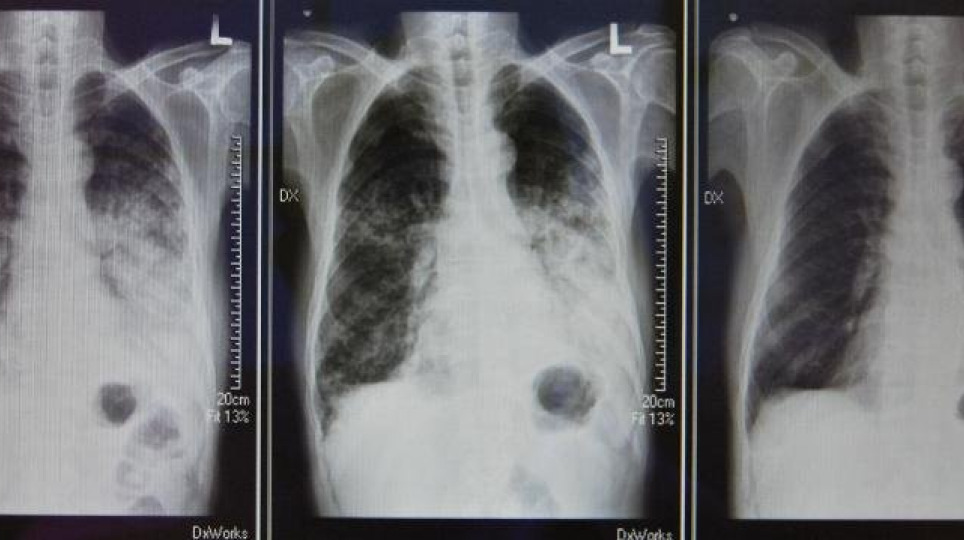

老菸槍得肺腺癌 使用標靶藥物病情好轉